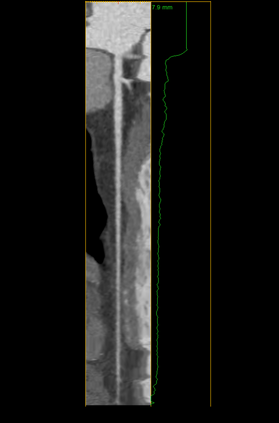

The standard non-invasive imaging technique used to assess the severity and extent of Coronary Artery Disease (CAD) is Coronary Computed Tomography Angiography (CCTA). However, manual grading of each patient's CCTA according to the CAD-Reporting and Data System (CAD-RADS) scoring is time-consuming and operator-dependent, especially in borderline cases. This work proposes a fully automated, and visually explainable, deep learning pipeline to be used as a decision support system for the CAD screening procedure. The pipeline performs two classification tasks: firstly, identifying patients who require further clinical investigations and secondly, classifying patients into subgroups based on the degree of stenosis, according to commonly used CAD-RADS thresholds. The pipeline pre-processes multiplanar projections of the coronary arteries, extracted from the original CCTAs, and classifies them using a fine-tuned Multi-Axis Vision Transformer architecture. With the aim of emulating the current clinical practice, the model is trained to assign a per-patient score by stacking the bi-dimensional longitudinal cross-sections of the three main coronary arteries along channel dimension. Furthermore, it generates visually interpretable maps to assess the reliability of the predictions. When run on a database of 1873 three-channel images of 253 patients collected at the Monzino Cardiology Center in Milan, the pipeline obtained an AUC of 0.87 and 0.93 for the two classification tasks, respectively. According to our knowledge, this is the first model trained to assign CAD-RADS scores learning solely from patient scores and not requiring finer imaging annotation steps that are not part of the clinical routine.